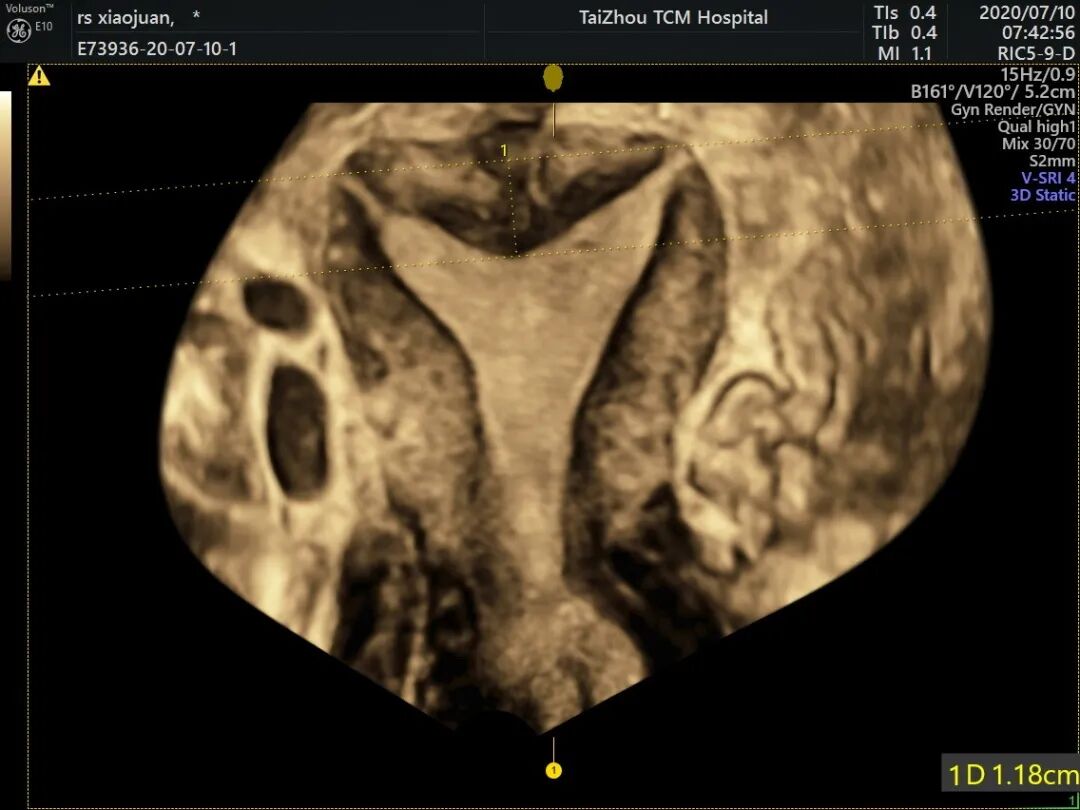

宫腔三维超声

宫腔三维可以使图像显示得栩栩如生,弥补了二维超声成像的不足,提供了丰富的立体空间信息,为疾病的诊断和治疗提供了进一步的帮助。

无创、准确性、可重复性、检查便捷。可以立体地、详尽地呈现子宫发育畸形类型、宫腔内病变位置及结构情况。

纵膈子宫